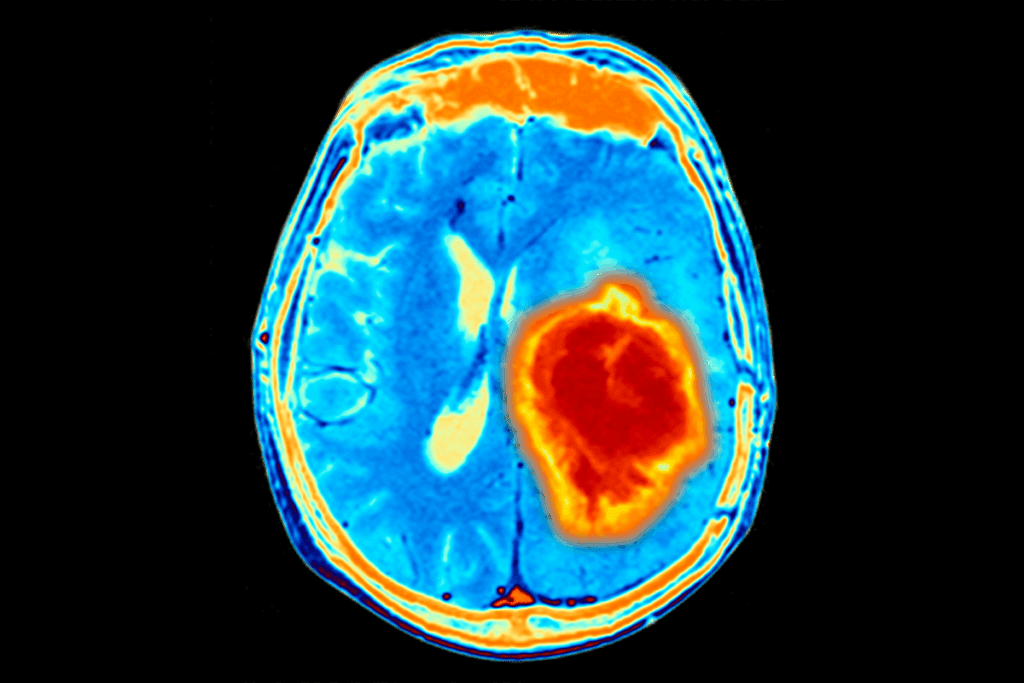

Advanced Imaging Techniques

Advanced imaging is vital for diagnosing brain tumors. Magnetic Resonance Imaging (MRI) is top choice because it’s sensitive and detailed, without radiation. It shows the tumor’s size and location.

Computed Tomography (CT) scans are used in emergencies. They’re quick but involve radiation and are less detailed than MRI.

| Imaging Modality | Advantages | Limitations |

| MRI | High sensitivity, detailed images, no radiation | Longer examination time, may require sedation |

| CT Scan | Quick, widely available | Involves radiation, less detailed than MRI |